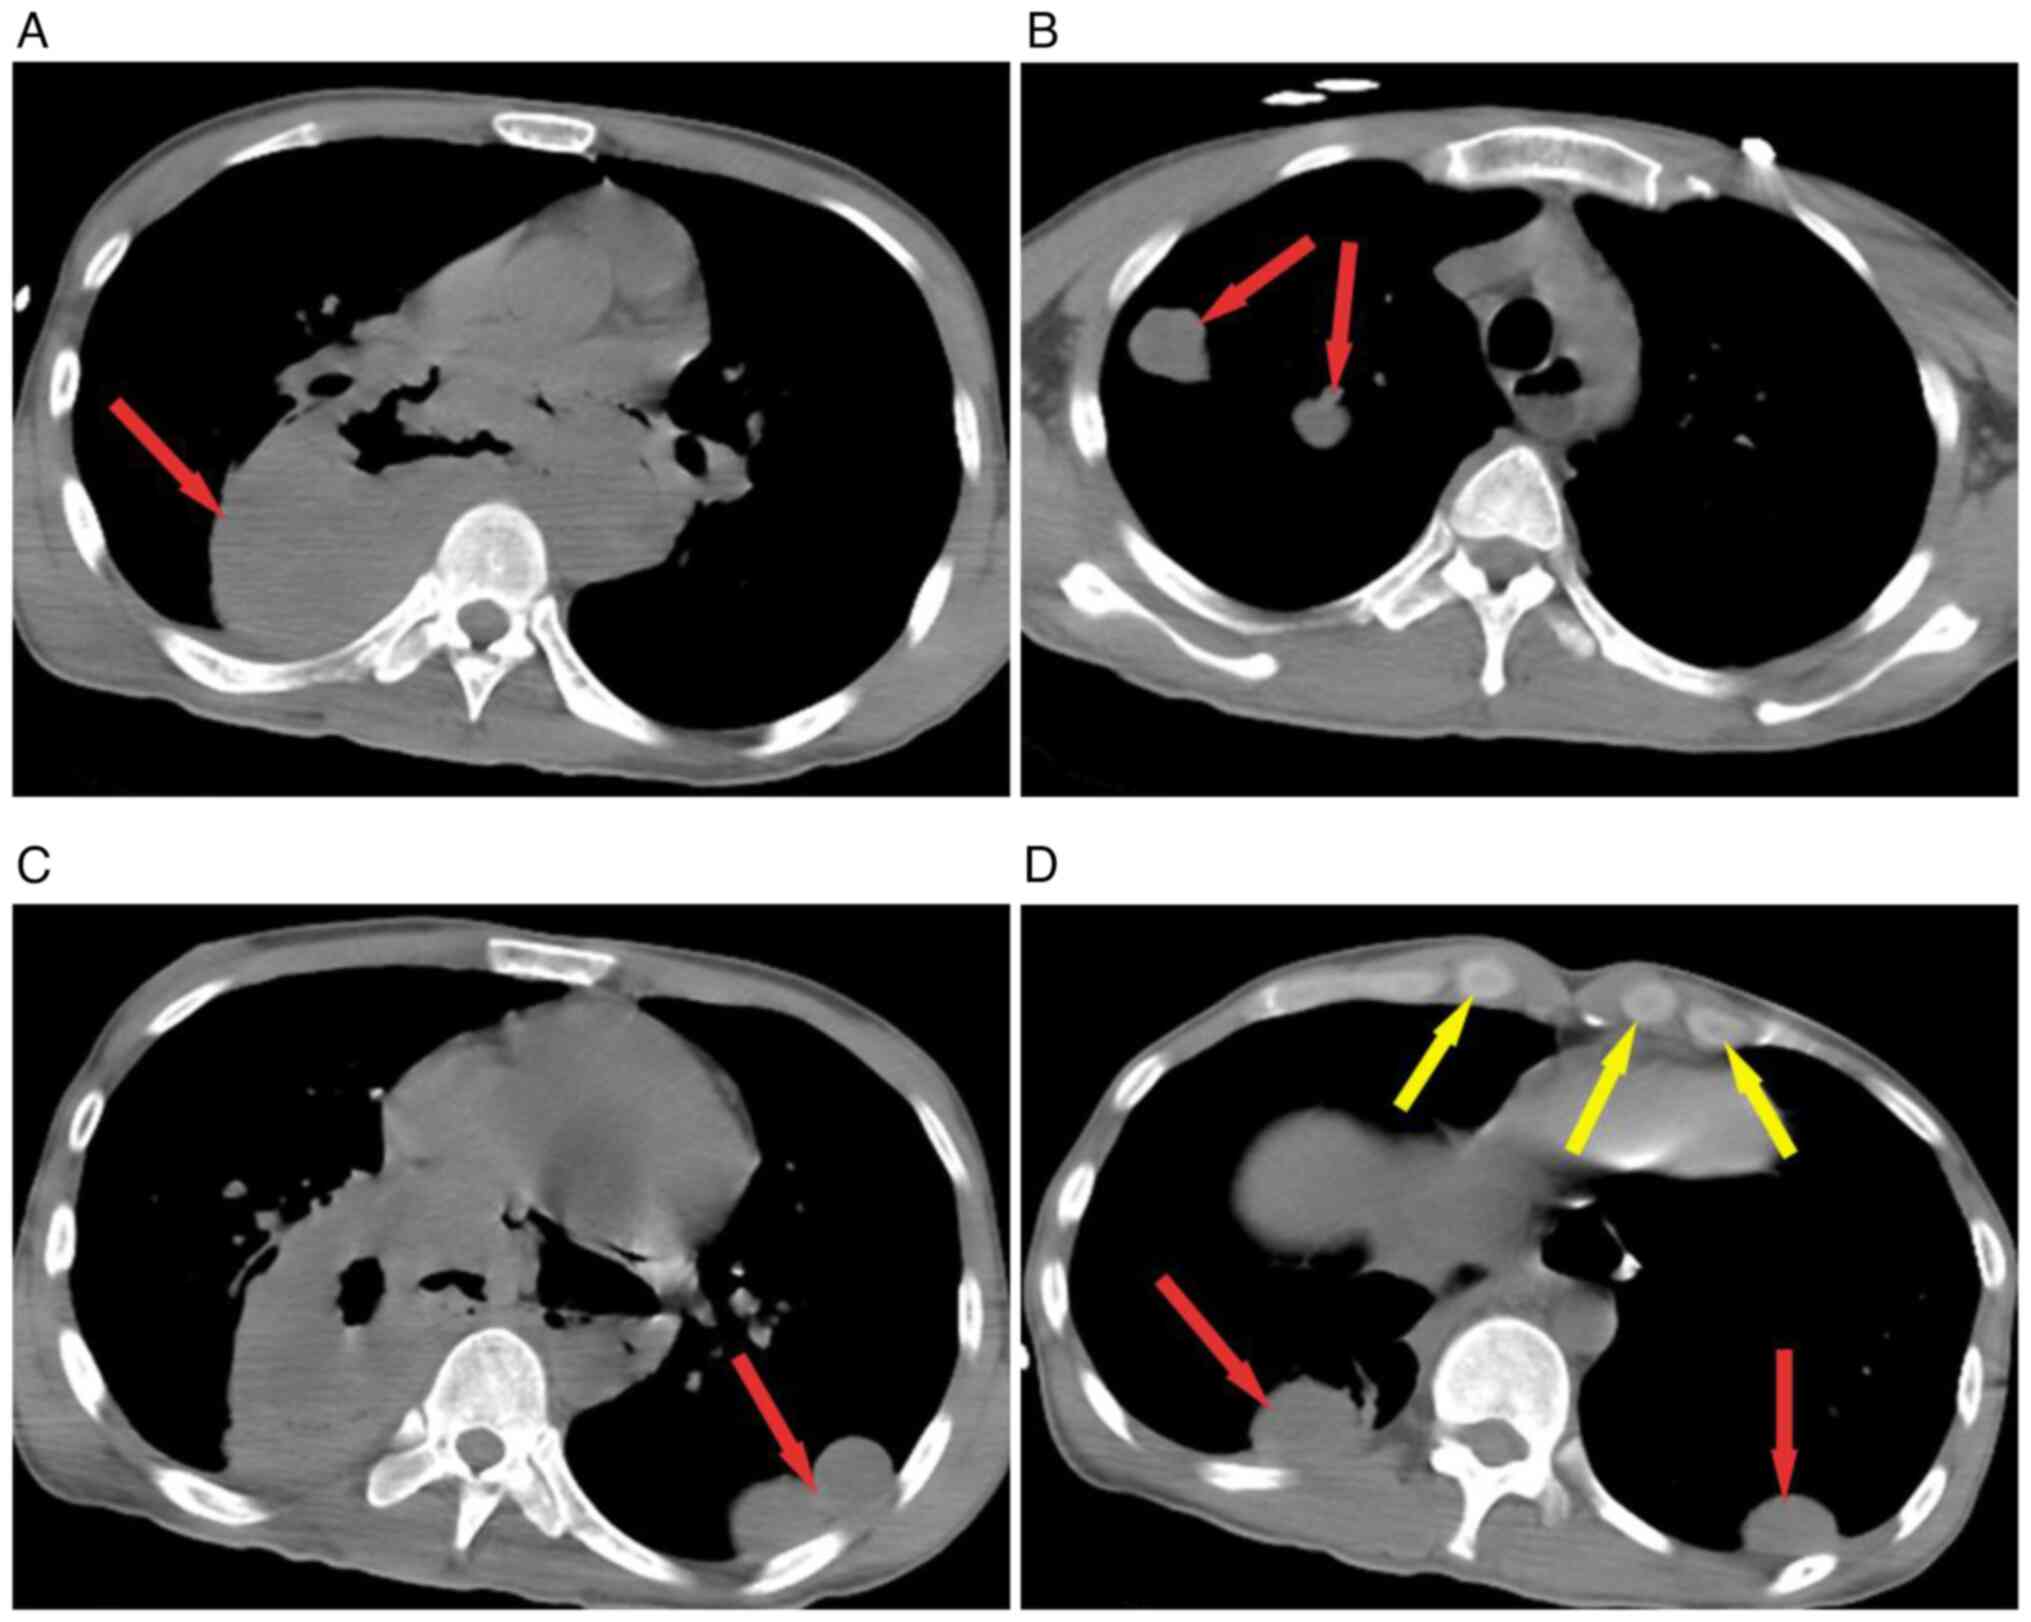

Figure 3

Chest CT changes in mediastinal window and lung window. (A) Chest CT scan showing a 13.6x6.6-cm huge mass with pneumatosis of the posterior mediastinal. (B and C) Multiple nodules (red arrows) of varying sizes are present in the upper and lower lobes of both lungs and the larger ones were ~3.5x2.7-cm in the lower lobe of the left lung. (D) Chest CT showing multiple nodules (yellow arrows) in both supraclavicular regions and the larger ones measuring ~1.8-cm in diameter. CT, computed tomography.

The authors followed up with the patient closely and learned that the patient had received systemic intravenous chemotherapy (carboplatin + paclitaxel) and anti-HIV therapy (tenofovir disoproxil, lamivudine and efavirenz) at other hospitals. Anti-HIV regimens included tenofovir disoproxil (doses: 300 mg/QD), lamivudine (doses: 300 mg/QD), and efavirenz (doses: 400 mg/QD). However, one month later, the patient developed drug intolerance, so tenofovir disoproxil (doses: 300 mg/QD) was replaced with zidovudine (doses: 300 mg/BID). Afterwards, the patient's drug intolerance improved, and the three drugs were continuously administered orally. In addition, the patient also received systemic intravenous chemotherapy, including carboplatin (250 mg /m2) and paclitaxel (175 mg/m2) for 21 days. The fourth chemotherapy session ended in mid-December. The patient was readmitted to Taihe Hospital, (Hubei, China) due to fever and dyspnea, and contrast-enhanced CT of the chest revealed carcinoma metastasis in both the lungs and mediastinum, including the bilateral supraclavicular lymph node. A markedly enlarged posterior mediastinal mass with air accumulation (esophageal fistula?) was noted (Fig. 3). Subsequently, an esophago-mediastinal fistula was confirmed by esophagography. Septic shock was cured with antibiotics (Merpenem, 1 g, iv, Q8h + teicoplanin, 0.4 g, iv, QD), intravenous nutritional support, fluid resuscitation and multiorgan system life support, but intermittent fever was still present. The patient was discharged after five days and transferred to an infectious disease hospital for further treatment. Then the patient was lost to follow-up after 5 months.